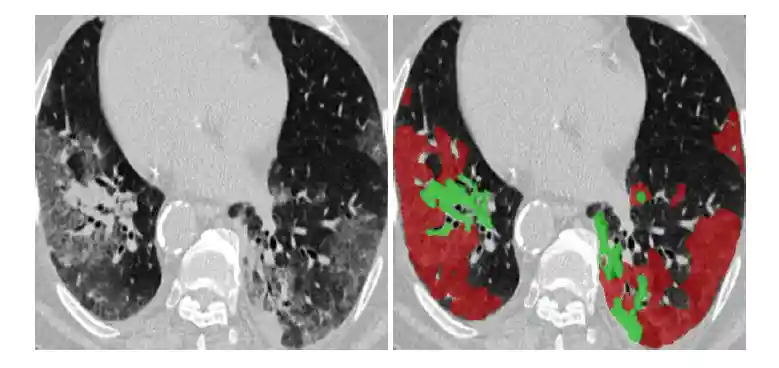

Figure 8: Lung Infection Segmentation.

Figure 9: Example of COVID-19 infected regions in CT axial slice, where the red and green regions denote the GGO,

and consolidation, respectively. The images are collected from here.

(COVID-19 CT segmentation dataset (link: https://medicalsegmentation.com/covid19/, accessed: 2020-04-11).)